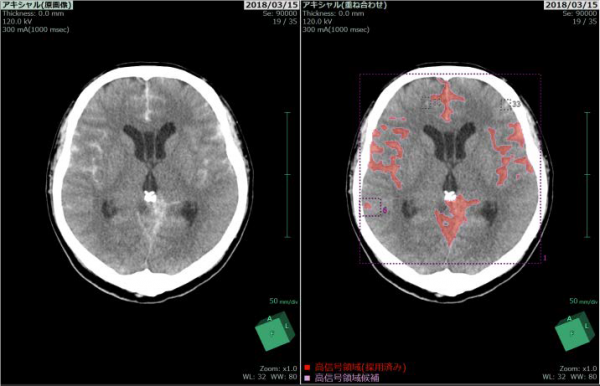

1.高信号領域・低信号領域の強調表示

頭部CT画像の高信号および低信号領域に色をつけて強調し表示される。これらは脳内の出血領域や虚血範囲の評価に用いられ、頭部CT画像診断の支援に繋がることが期待されている。

左 画像解析前

右 画像解析後

高信号領域(画像上、周囲と比べて白っぽい領域)を強調して赤色で表示する。